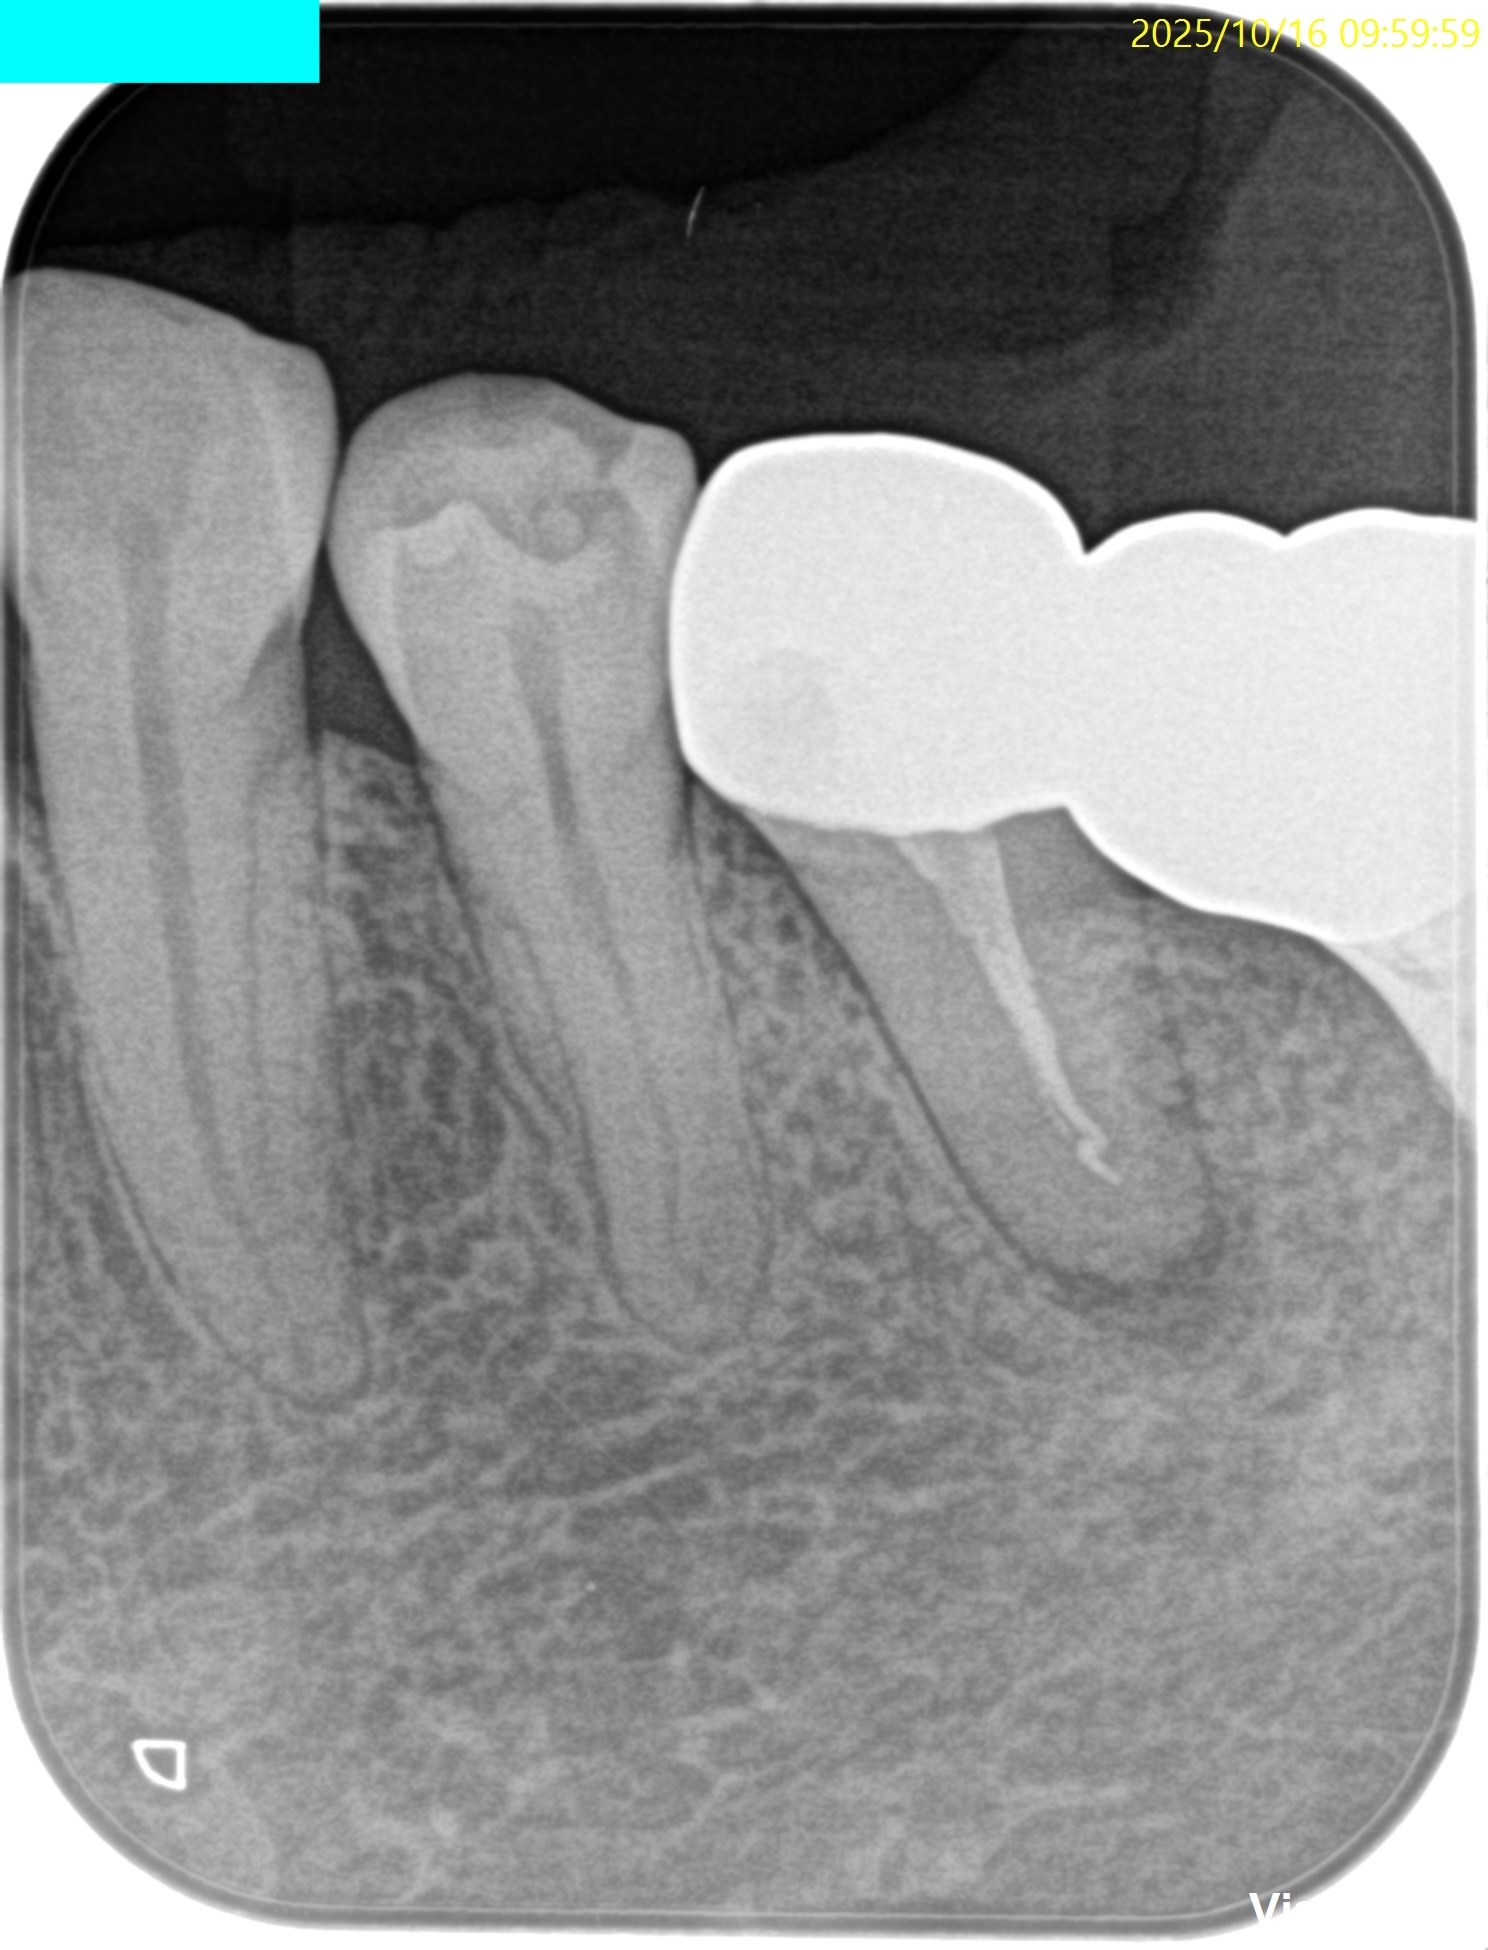

検査とPAは以下である。

またPAではなるほど、歯内療法の問題があるとわかる。

根管充填も根尖部は疎でGutta Percha PointがKink(豚の尻尾)になっている。

根充時にそのポイントよりも先に行かないので他院での治療でそれを押し込めたのだろう。